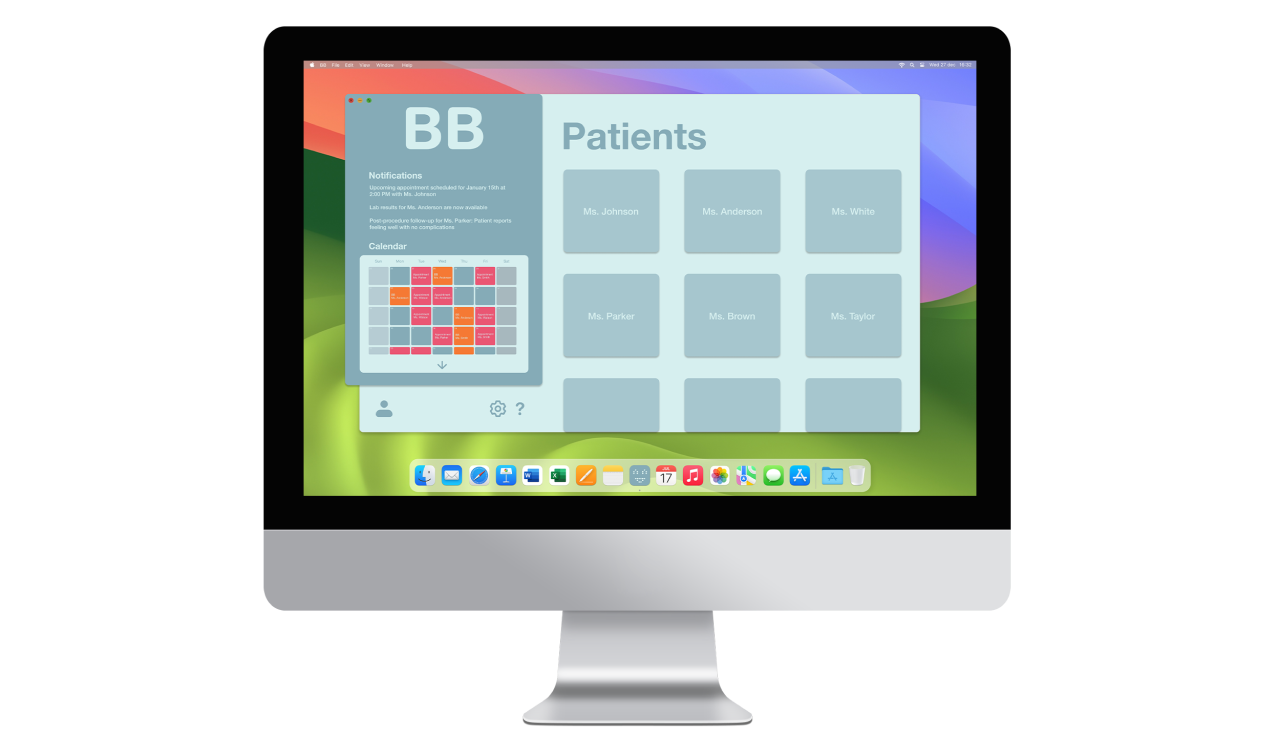

(2) B-B [product-service system for pregnancy monitoring]

B-B is a product-service system that connects pregnant women with their gynecologists through a monitoring device that tracks key health parameters while strengthening the emotional bond with the unborn child. It fosters closer relationships and more holistic, emotionally connected prenatal care.

The gynecologist’s user experience prioritizes minimal invasiveness and comfort, incorporating alert notifications for irregularities during monitoring. Additionally, a desktop interface allows access to data reports and appointments, benefiting both gynecologists and administrative staff. Administrative access enables efficient scheduling of device activations, enhancing coordination within the healthcare system.